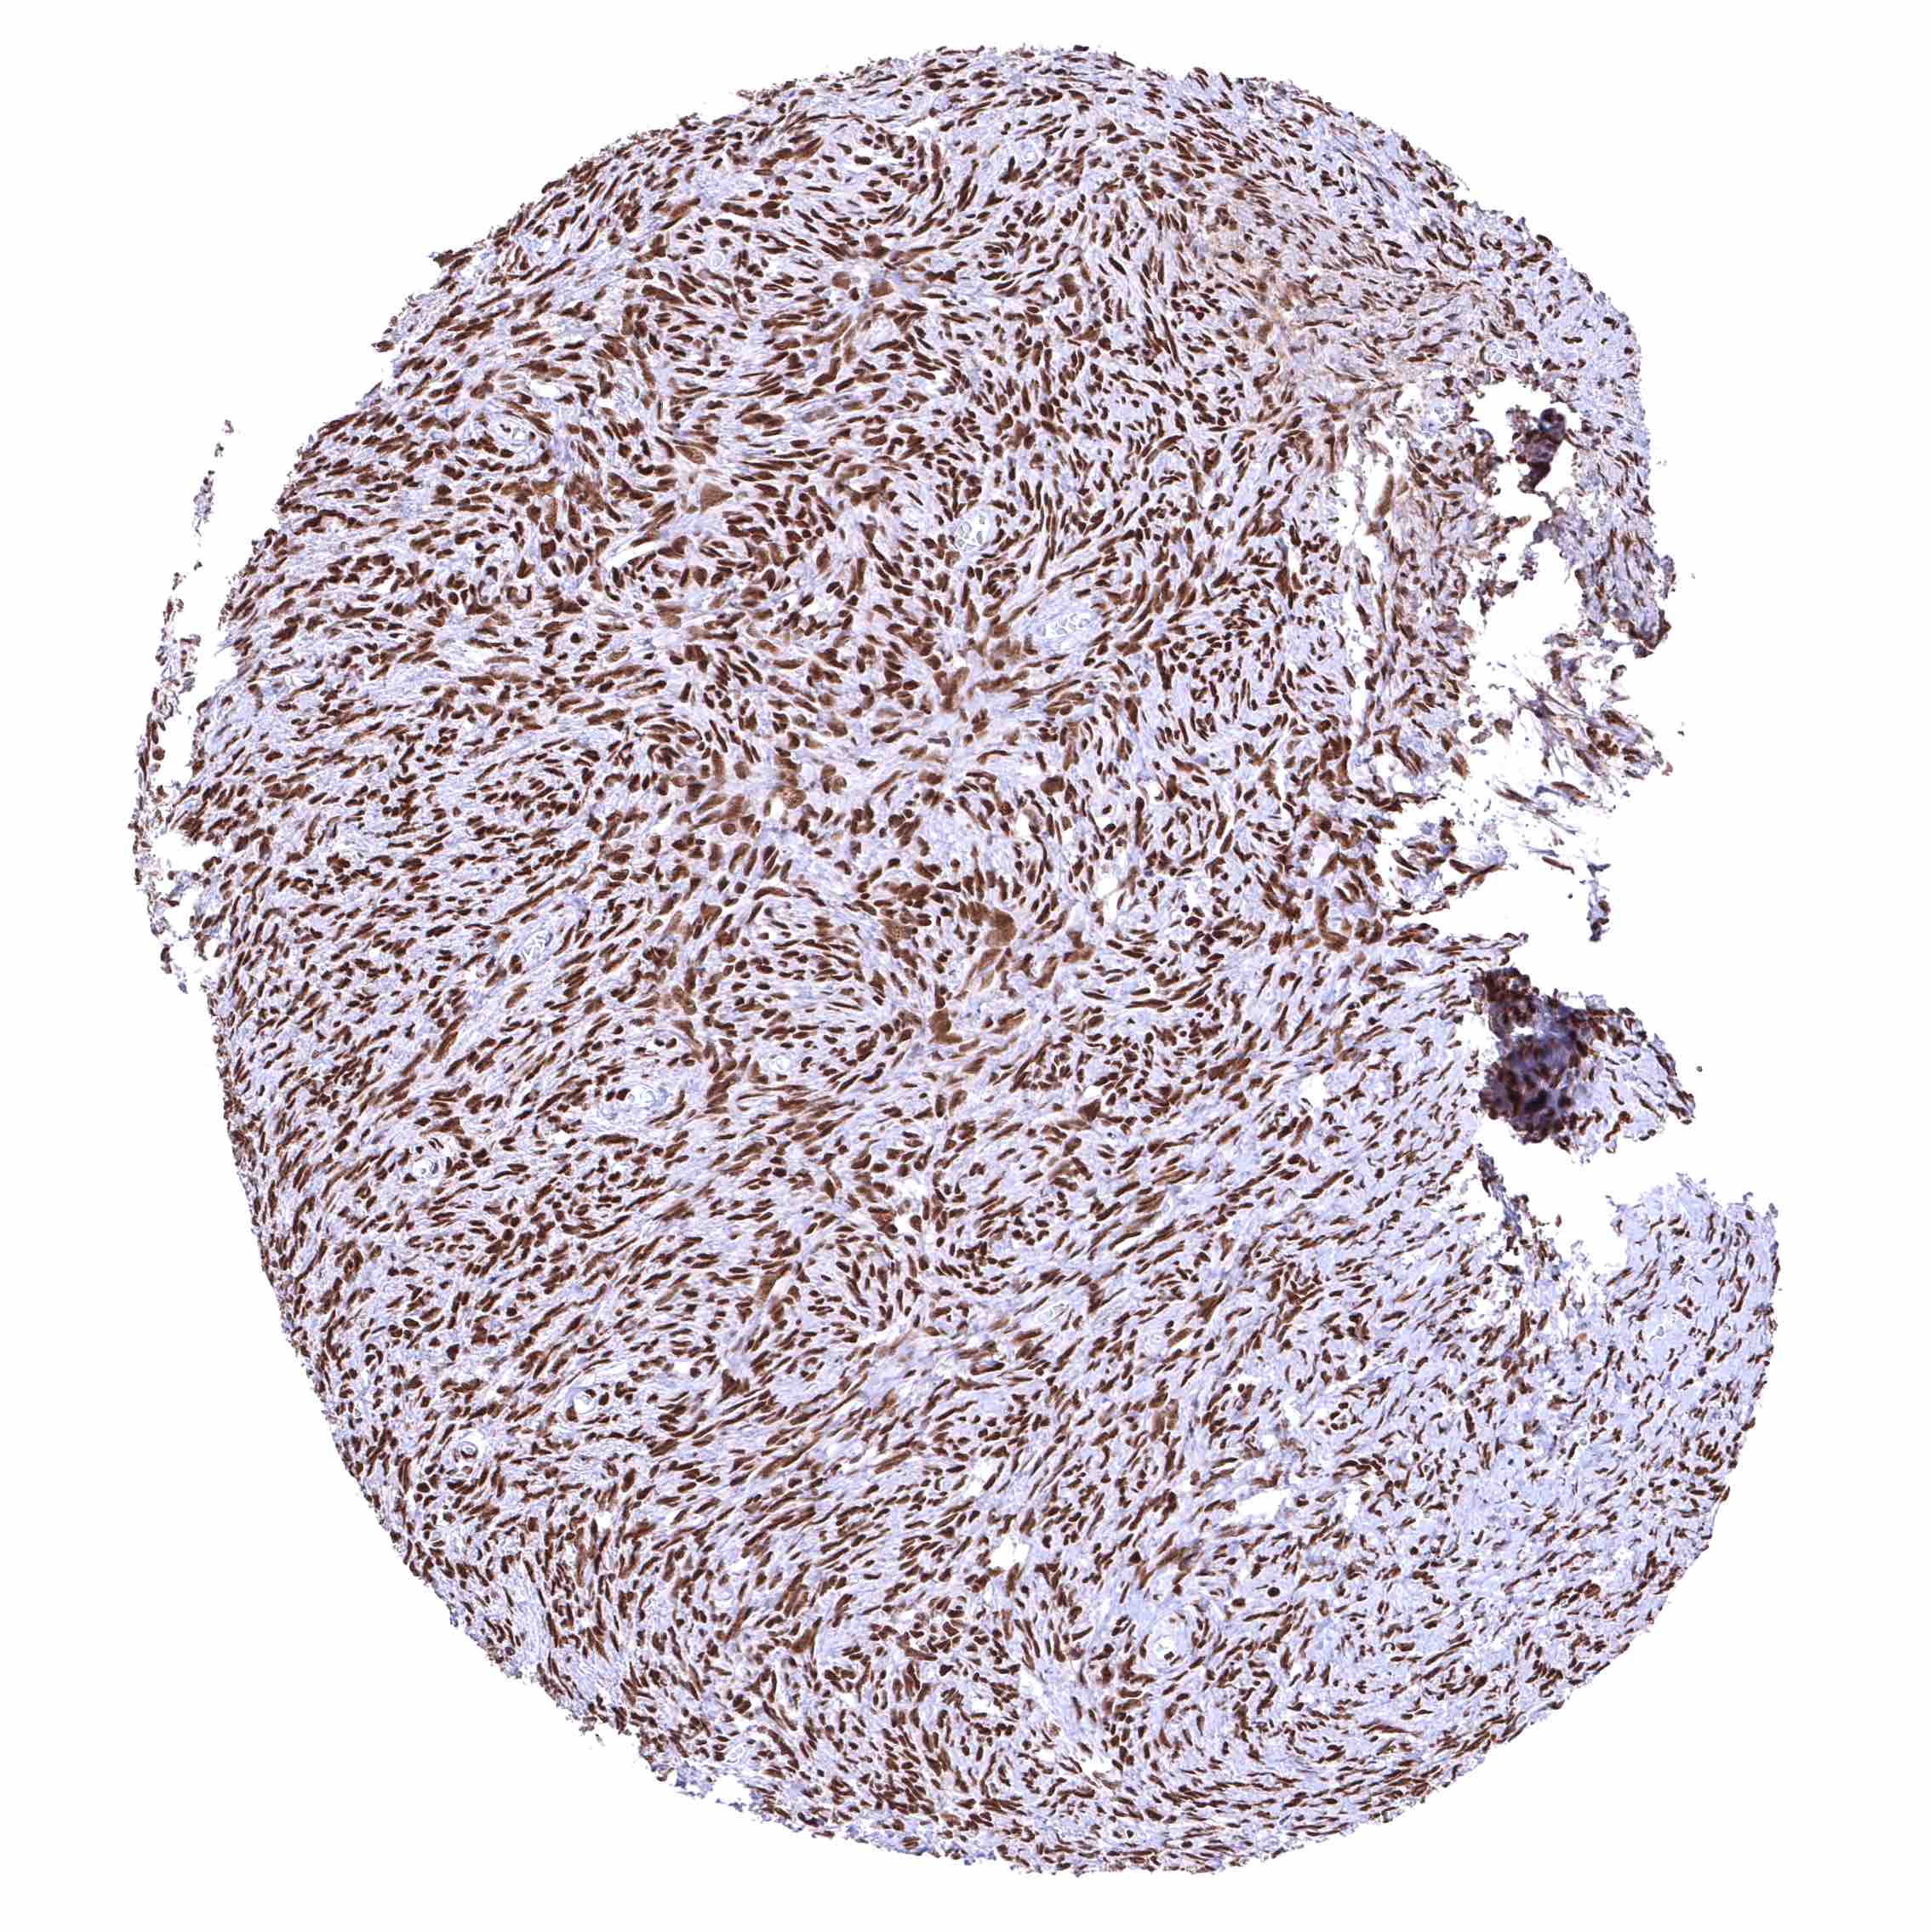

Uterus, myometrium – Distinct nuclear BRD4 staining of all muscle cells.